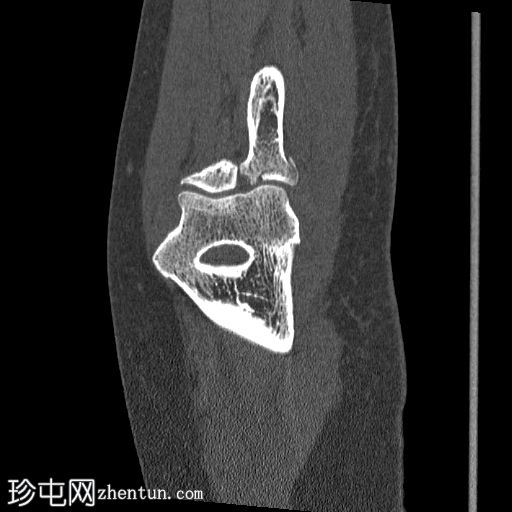

轴向骨窗

显示整个桡骨头粉碎性骨折,特征为两个以上大骨折块,以及倾斜且受压的关节节。

这表明该骨折为不稳定骨折,根据Mason桡骨头骨折分型,为IIIC型。

远端肱骨和可见尺骨未见骨折征象。

此外,由于关节积血导致关节扩张,肘关节脂肪平面弯曲。